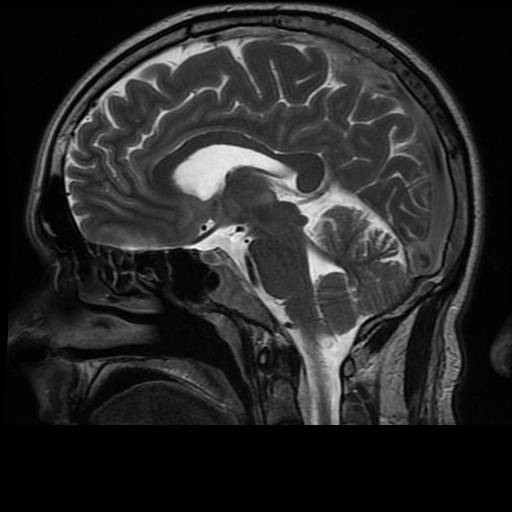

Billede 3: Normal hjerne, sagittalt snit (set fra siden).

MR-billederne viser fire forskellige optagelser af en normal hjerne. Cerebrospinalvæsken er hvid på billede 1 og 3, mens den er sort på 2 og 4. Man ser tydeligt forskellen på grå og hvid substans i hjernen, det ses bedst på 2 og 4.